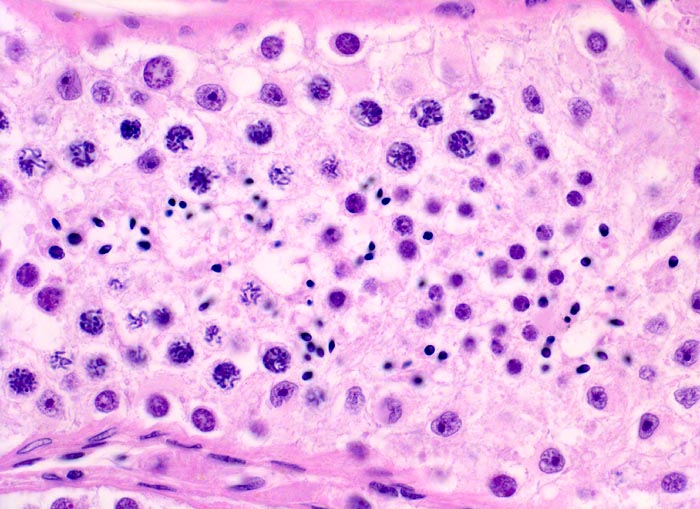

Spermiogenese

Normalbefund

Hoden

Normal ausreifende Spermiogenese. Spermatogonien. Primäre Spermatozyten im Präleptotän. Primäre Spermatozyten im Zygotän/Pachytän. Spermatiden. Unreife Spermatozoen. Sertolizellen sind lichtmikroskopisch nicht sicher abgrenzbar.

Klassisches Seminom

400

43